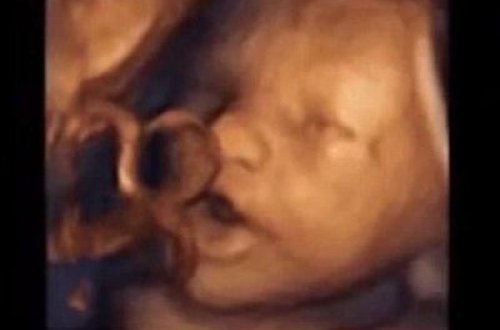

Elmdə SENSASİYA

822

musiqini

musiqi

ayırd

sonra

professor

bətndəki

qadınların

krpə

oxumağa

bətnindəki

krpələr

etmiş

eşidir

səsini

faizinin

mariza

başılıq

lopes

araşdırmaya

eşidəndə